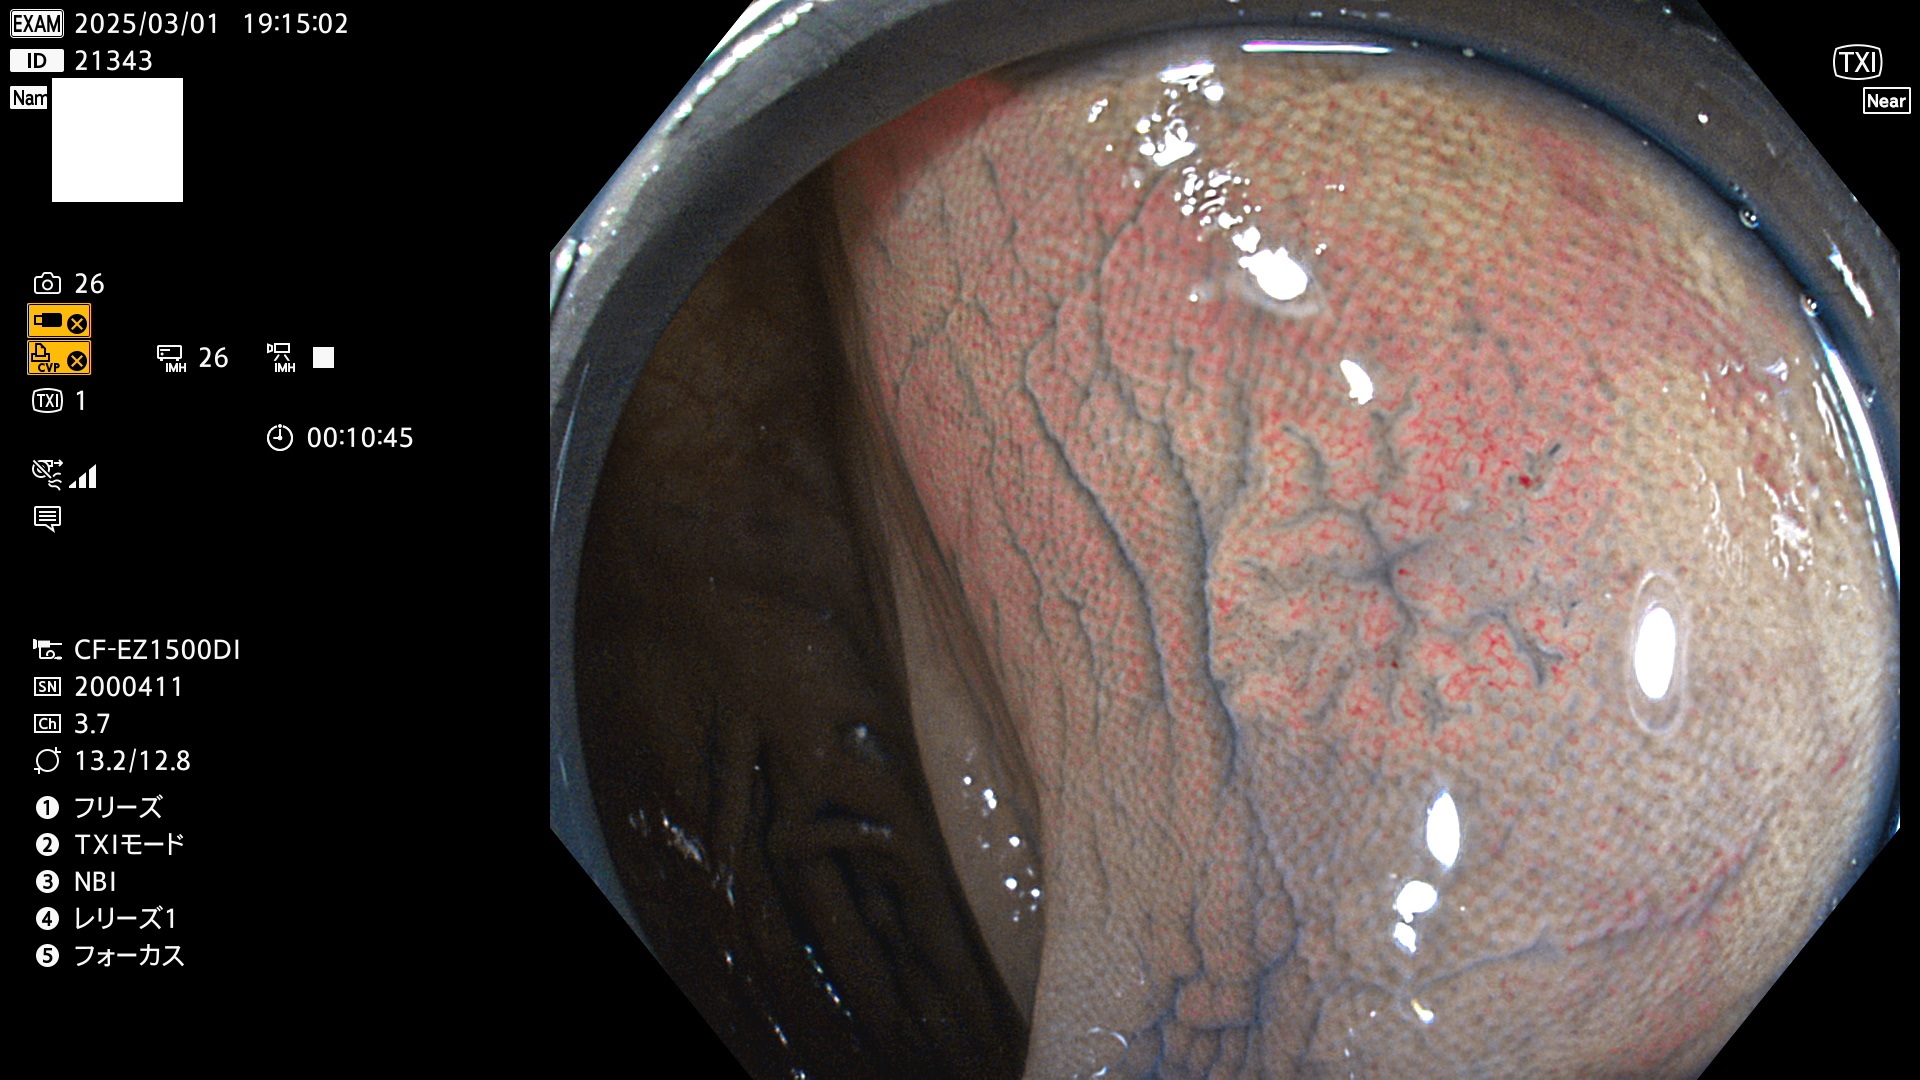

今週のUb、Uc型腺腫

完全に平坦な物をUb、陥凹している物をUcと呼びます。最も発見が難しく危険な病変です。

毎週の検査(木・金・土・日)に発見されたUb、Uc型・腺腫を、その週の日曜の夜にUPし1週間、提示します。

抽出の対象期間 2025年2月27日〜3月2日の4日間(48件の検査)9個 (9/48=19%)